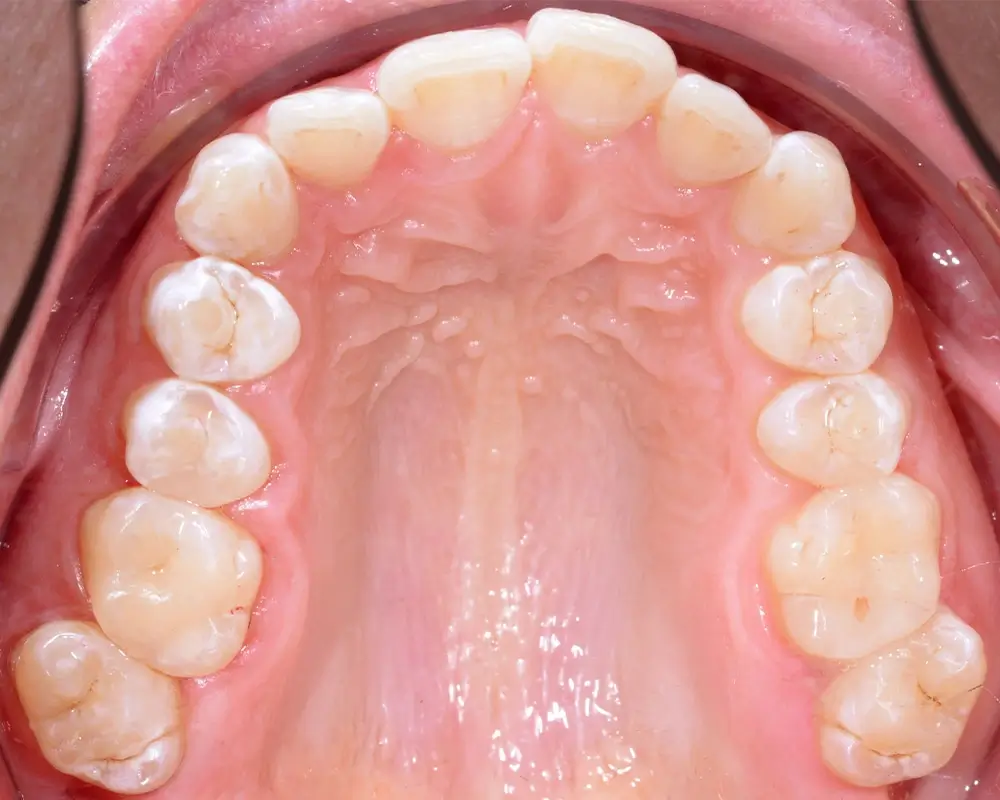

Кейс 1

Количество кап ВЧ 25

Количество кап НЧ 25

ДО

ПОСЛЕ